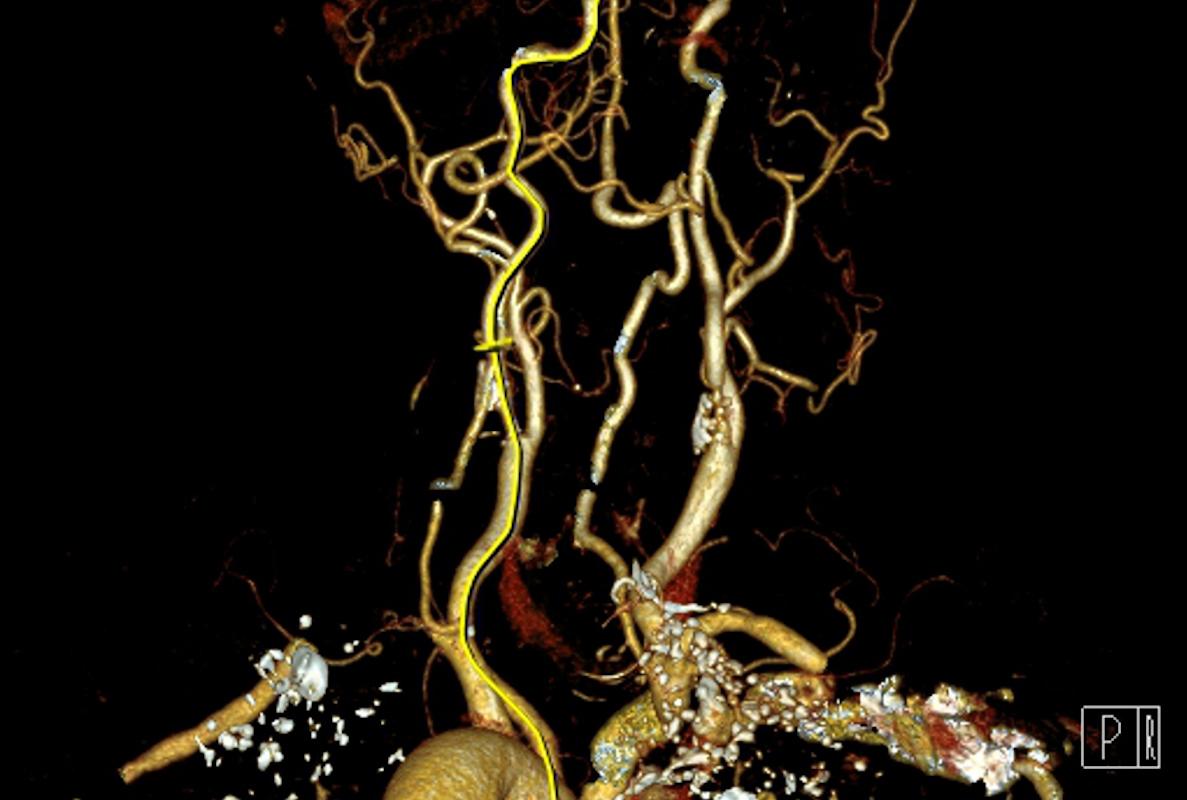

Restaure le flux sanguin

Des chercheurs ont identifié un composé chimique qui permet d’éviter la formation de plaques dans le cerveau, et préserve la circulation sanguine.

De nouvelles pistes dans le traitement d’Alzheimer. Une équipe de chercheurs tente d’éviter la formation de caillots sanguins dans le cerveau des malades. Ils développent actuellement un composé qui agit dans ce sens, rapporte une étude à paraître dans l’édition de juillet de Nature Reviews Drugs Discovery. Connu sous le nom de RU-505, il permettrait aux malades de récupérer un flux sanguin et une coagulation proches de la normale.

Avec un apport sanguin réduit, les neurones fonctionnent moins bien. Dans la maladie d’Alzheimer, les chercheurs ont longtemps soupçonné que les plaques formées par la protéine bêta amyloïde réduisaient le flux sanguin… et favorisaient la formation de caillot. Des soupçons confirmés par la recherche : la bêta amyloïde se lie à l’agent coagulant fibrinogène. Cela contribue à la perte de mémoire, la confusion et le déclin cognitif.

Un composé chimique est actuellement scruté au microscope : le RU-505. Il permettrait d’interférer avec la bêta amyloïde et éviterait la formation de plaques entre les neurones. Mais ce composé bloque aussi l’interaction entre la protéine et l’agent coagulant, comme l’explique Sidney Strickland, principal chercheur : « Nos expériences in vitro et sur la souris ont montré que le composé, connu comme le RU-505, aide à restaurer une coagulation et un flux sanguin cérébral normaux. Mais le plus gros gain est apparu lors des tests comportementaux sur les souris traitées, qui ont une meilleure mémoire que leurs pairs non traités. Ces résultats suggèrent que nous avons trouvé une nouvelle stratégie avec laquelle traiter Alzheimer », explique-t-il.

Les souris traitées souffraient moins d’inflammation chronique. Le flux sanguin dans le cerveau des animaux était aussi plus proche de la normale. Placés dans un labyrinthe, ces rongeurs avaient de meilleurs résultats que leurs pairs non traités : ils identifiaient plus rapidement la sortie et y parvenaient dans de meilleurs délais, même après un entraînement.